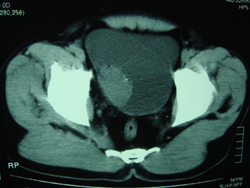

典型病例,男,56岁。无痛性血尿3月。

膀胱占位性病变,呈菜花状生长,考虑膀胱癌。 期待病理。